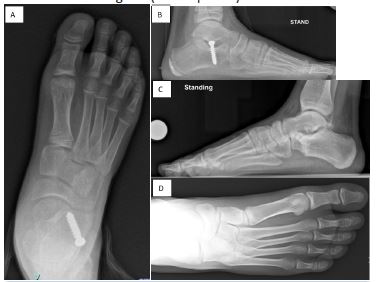

The mean follow-up for the arthroereisis group was 38.2 months (range, 12–78 months). The mean preoperative talonavicular coverage angle was 19.2° (range, 8°–31°) compared with 5.1° (range, 0°–10°) postoperatively (p<.0001; Table 2). The mean calcaneal pitch angle improved from 8.3° (range, 0°–14°) preoperatively to 16.7° (range, 7°–26°) postoperatively (p<.0001). The mean Meary’s angle improved from –11.3° (range, –21° to –5°) preoperatively to 1.9° (range, –4° to 4°) postoperatively (p < .0001; (Figure 4 A, B). The mean AOFAS score increased from 57.2 (range, 47–67) preoperatively to 92.2 (range, 80–100) postoperatively (p<.0001). Clinical outcome according to the AOFAS score was rated excellent (90–100 points) in 14 of 18 feet and good (80–87 points) in 4 feet.

Figure 4: Corrected talo-navicular coverage, calcaneal pitch and Meary’s angle after calcaneal lengthening osteotomy (A,B) and arthroereisis (C,D).

The mean follow-up for the CLO group was 30.1 months (range, 14–69 months). The mean preoperative talonavicular coverage angle was 22.3° (range, 10°–32°) compared with 2.8° (range, 0°–9°) postoperatively (p<.0001; Table 3). The mean calcaneal pitch angle improved from 9.7° (range, 5°–16°) preoperatively to 20.4° (range, 14°–26°) postoperatively (p<.0001). The mean Meary’s angle improved from –5.6° (range, –15° to 0°) preoperatively to 4.2° (range, 0°–10°) postoperatively (p<.0001 (Figure 4 C, D). The mean AOFAS score increased from 60.4 (range, 55–72) preoperatively to 92.6 (range, 87–97) postoperatively (p<.0001). Clinical outcome according to the AOFAS score was rated excellent (90–100 points) in 25 feet and good (80–89 points) in 2 feet.

The magnitude of improvement in clinical and radiographic parameters was calculated as the difference between preoperative and postoperative values for both procedures (Table 4). The mean increase in AOFAS score was 35.1 points in the arthroereisis group compared with 32.2 points in the CLO group (p=.14). The calcaneal pitch angle improved by 8.4° in the arthroereisis group and by 10.7° in the CLO group (p=.07). The mean change in Meary’s angle was 13.8° after arthroereisis and 9.8° after CLO (p<.01). The talonavicular coverage angle improved by 19.5° in the CLO group and by 14.1° in the arthroereisis group (p<.01).